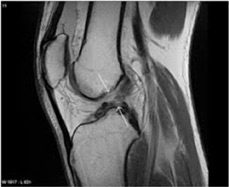

La decisión de si se debe operar, no sólo depende de los resultados de estudios complementarios (resonancia nuclear magnética), sino también del examen físico y de la sintomatología del paciente (sensaciones de inestabilidad o si se le sale la rodilla).

Las técnicas quirúrgicas son artroscópicas (visualización de una articulación), empleando para la reconstrucción del ligamento cruzado anterior injertos autólogos (del mismo paciente) de tendones isquiotibiales, tendón rotuliano o tendón cuadricipital, como aloinjertos (provenientes de donantes).